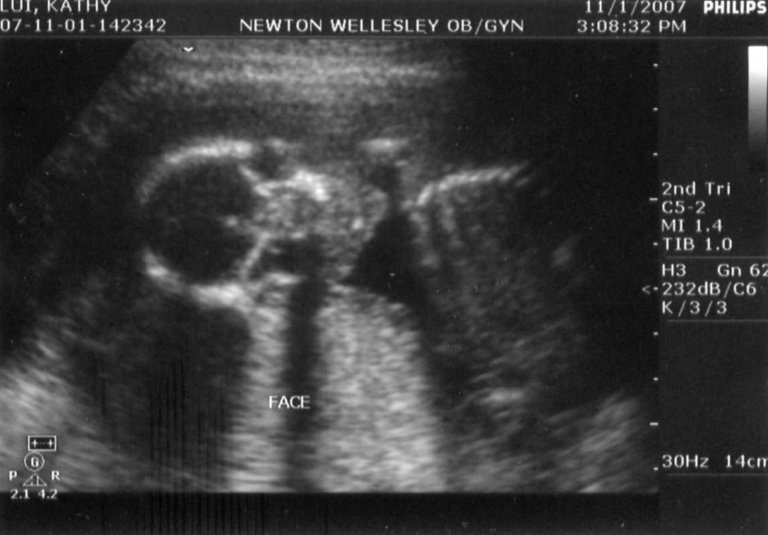

These were back at the doctor's office. Bascially, they did the same set of tests as the Maternal-Fetal medicine folks did the previous week. This appointment had been scheduled about a month in advance, before both phases of the integrated screening had been conducted at the hospital. According to my obstetrician, the results looked good. Again, we got a good guess as to the sex.